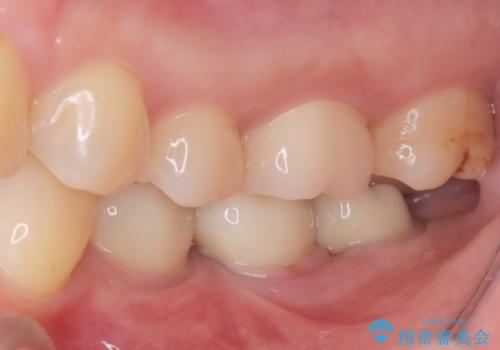

2回で完了した奥歯のセラミック修復

- 奥歯の虫歯治療を主訴にご来院されました。患者様から「できるだけ通院回数を少なく、早く治療を終わらせたい」というご要望があったため、短期間での完了を目指し、セラミックインレー(詰め物)とセラミッククラウン(被せ物)を併用する治療計画を立案しました。治療は精密機器を活用し、2回の来院で最終的なセラミック修復物を装着することを目指します。

今回の治療では、虫歯の大きさや深さに応じて、異なるセラミック修復法を適用しました。

比較的軽度な虫歯には、セラミックインレー(詰め物)で対応し、健全な歯質を最大限に残しました。

進行した虫歯や歯の強度が低下している歯には、セラミッククラウン(被せ物)を選択し、歯全体を保護することで破折を防ぎました。

短期間での治療を可能にしつつ、天然歯と見分けがつかない審美性と、長期的に安定する機能性を兼ね備えたセラミック修復を実現しました。